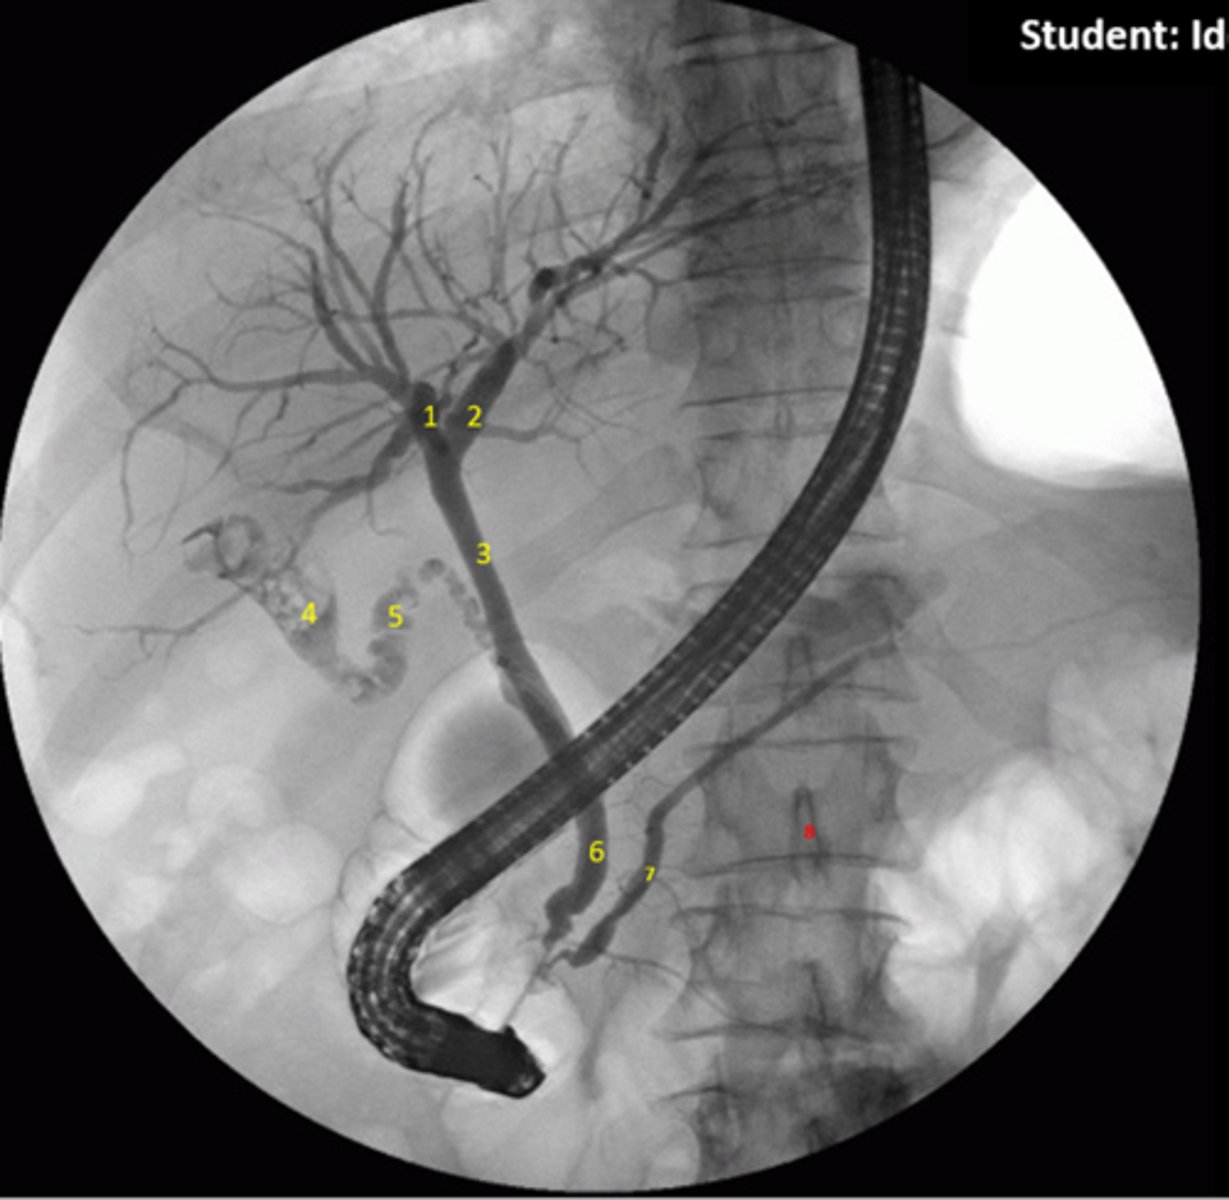

Identify indicated anatomy in the following radiograph

1.Right hepatic duct

2.Left hepatic duct

3.Common hepatic duct

4.Gallbladder

5.Cystic duct

6.Common bile duct

7.Pancreatic duct

8.Spinous process

<p>1.Right hepatic duct</p><p>2.Left hepatic duct</p><p>3.Common hepatic duct</p><p>4.Gallbladder</p><p>5.Cystic duct</p><p>6.Common bile duct</p><p>7.Pancreatic duct</p><p>8.Spinous process</p>